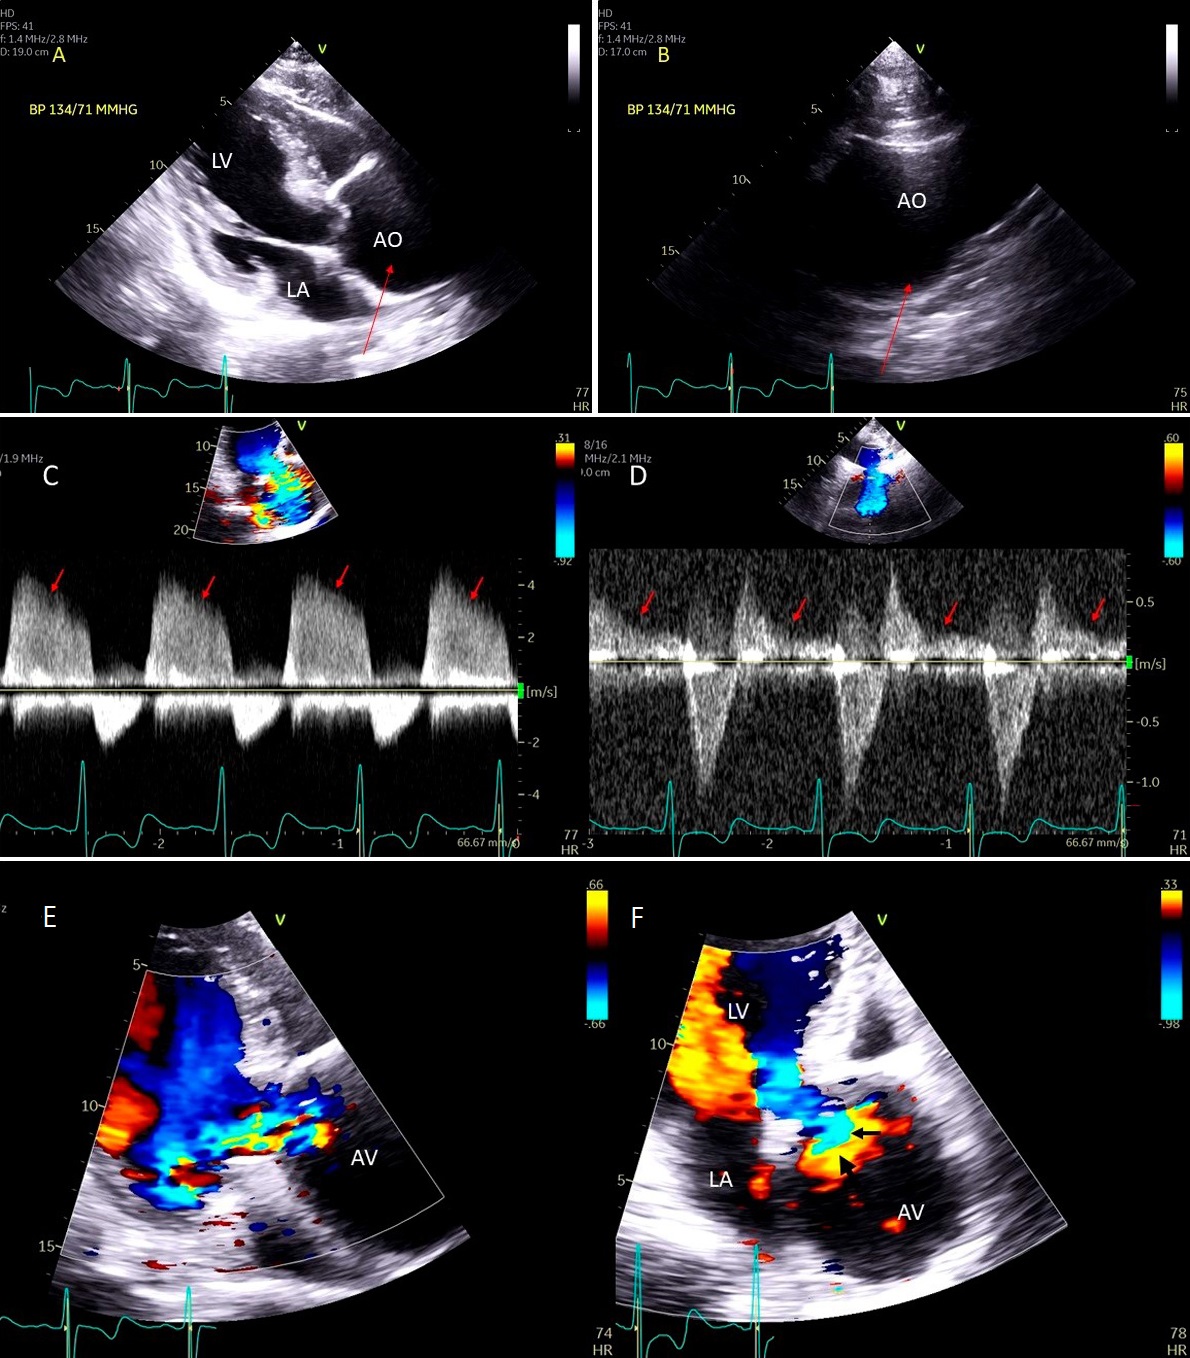

Fig. 9.Aortic valve regurgitation induced by dilated annulus. (A)

Transthoracic echocardiogram parasternal long axis view showing

markedly dilated aortic sinuses (red arrow). (B) Imaging at a higher parasternal window shows aneurysmal aortic sinuses (red arrow)

and normal ascending aorta above sinotubular junction.

(C) Three chamber view with continuous-wave (CW) Doppler showing dense AI Doppler

envelope with a steep deceleration slope (red arrows) suggesting severe AI. (D) CW Doppler recording at the proximal descending thoracic aorta

demonstrating pandiastolic flow reversal (red arrows), another feature of severe AI.

(E) Color Doppler parasternal long axis view showing AI color

jet occupying two third of the LV outflow tract with a wide vena contracta at origin from the aortic valve leaflets (

TTE is an essential first diagnostic tool and is frequently sufficient to assess the presence and severity of AR [60]. Besides an assessment of the aortic valve and aortic root anatomy to determine the etiology of the regurgitation, assessment of AR should include evaluation of LV size, geometry, and function [5]. In chronic AR, TTE is essential in monitoring the changes in LV geometry (LV size and LV volume increase) and function (progressive worsening LV function) due to the prolonged LV volume overload. LV dilatation, particularly with preserved LV function, is a supportive sign of significant AR and becomes more specific excluding other causes of LV volume overload (e.g., in athletes, anemia). In severe acute AR, the LV is not dilated, and the LV end-diastolic pressure increase may cause the MV premature closure, best documented with an M-mode.

Common causes of leaflet malfunction causing AR include degenerative leaflet calcifications, and infective endocarditis (Fig. 10), bicuspid aortic valve perforation and rheumatic fever. The causes of AR include Marfan’s syndrome, annulo-aortic ectasia (idiopathic root dilatation) (Fig. 9), aortic dissection, connective tissue disease, and syphilis. The Carpentier classification is also widely used to describe the mechanism of AR [63].